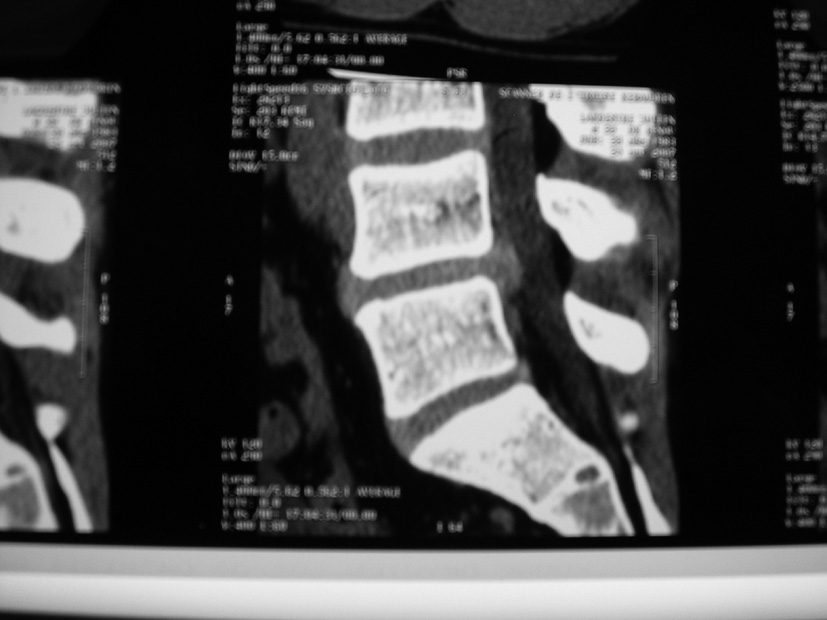

Décrivez l’image scanographique. Est-elle compatible avec le tableau clinique ?